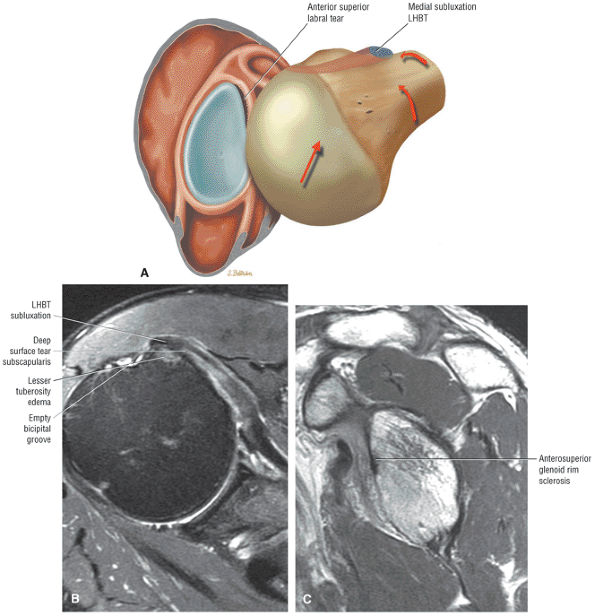

FIGURE 8.30 ● Axial images through the AC joint should be obtained on all shoulder MR examinations. (A) Axial T1- or PD-weighted images at this location are used to identify fractures of the distal clavicle and to demonstrate an os acromiale. (B) Axial FS PD-weighted images show cartilage covering the distal aspect of the clavicle and the medial aspect of the acromion at the AC joint. Cartilage defects and thinning, as well as subchondral bone marrow edema and cystic change, are evaluated on axial images through the AC joint. These degenerative changes can mimic the symptoms of a rotator cuff tear. (C) Axial T1- or PD-weighted images demonstrate the Hill-Sachs lesion of the humeral head, usually visualized as focal flattening or concave deformities in the posterolateral humeral head. The Hill-Sachs lesions is identified on the first or second superior axial image through the humeral head. Subcortical cystic change is more commonly visualized in the posterolateral humeral head and is usually an incidental finding in asymptomatic patients. (D) Axial FS PD-weighted images depict the biceps tendon coursing across the anteromedial aspect of the humeral head, within the rotator interval. This image location serves as a starting point for following the remainder of the biceps tendon into the bicipital groove on successive axial images moving from cranial to caudal. Tears of the supraspinatus and infraspinatus tendons are also identified at this image location on axial images. (E) Axial T1- or PD-weighted images allow evaluation of subcoracoid impingement. (F) In this location, thickening and increased signal in the superior glenohumeral ligament and coracohumeral ligament on an axial FS PD-weighted image may indicate adhesive capsulitis, particularly when accompanied by thickening and increased signal within the inferior glenohumeral ligament. (G) Axial T1- or PD-weighted images are used to identify subcortical cystic change in the greater and lesser tuberosity. This finding is commonly an indirect indication of abnormality or tearing in the overlying distal supraspinatus and subscapularis tendons, respectively. (H) Axial FS PD-weighted images through the proximal bicipital groove are used to identify “hidden lesions,” which are diagnosed when the biceps tendon is medially subluxing out of the bicipital groove, usually into a distal subscapularis tear or anterior to the lesser tuberosity. A degenerated biceps tendon may appear flattened and elongated as it rounds the lesser tuberosity into the proximal bicipital groove. Commonly, only the medial “tail” of the flattened degenerated biceps tendon subluxes out of the groove; the remainder of the flattened biceps tendon stays within the groove. (I) Axial T1- or PD-weighted images display the osseous glenoid subchondral surface, which should appear flat. Osseous glenoid remodeling, hypertrophy, deformity, subchondral cystic change, and edema are commonly identified as indirect evidence of overlying chronic cartilage degeneration or prior trauma. Posterior glenoid spurring may completely replace a degenerated or markedly attenuated posterior labrum. (J) Axial FS PD-weighted images are optimal for displaying the glenoid and humeral head cartilage. Chondral fissures, thinning, and defects are visualized when viewing successive cranial-to-caudal images through the glenohumeral joint. The anterior and posterior labrum are also optimally visualized and are normally firmly adherent to the glenoid and glenoid articular cartilage. (K) Axial T1- or PD-weighted images are used to identify bony Bankart lesions. These lesions are seen on inferior axial images through the glenohumeral ligament as oblique fracture lines extending through the anterior inferior glenoid. (L) Axial FS PD-weighted images show the prominent anterior band of the IGHL, which is occasionally mistaken for a tear of the anterior inferior labrum when fluid is interposed between the anterior band and the normal labrum.